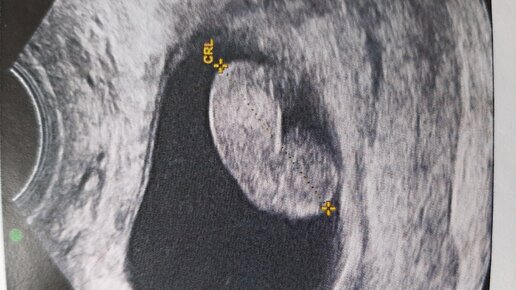

Эмбрион 5-6недель 3D реконструкция системы кровообращения эмбриона в 5-6недельзи-картина эмбриона в 5-6недель. УЗИ картина эмбриона в 5-6 недель Итак, говоря о развитии эмбриона, я не буду детально вдаваться в подробности развития тканей, зачатков органов и систем...